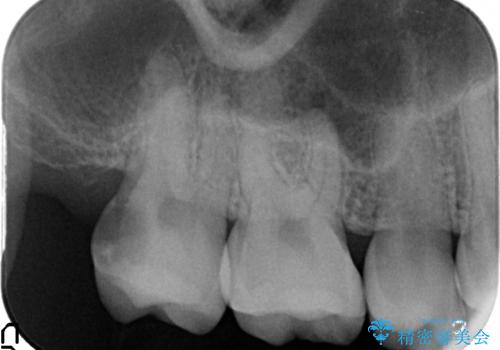

- 右上7の虫歯が大きく、他院にて抜歯と言われたが、なんとか残せないかと当院にいらっしゃった方の症例です。

自発痛の既往および持続痛を認めたため、カリエス除去後根管治療を行いました。

その後オールセラミッククラウンによる補綴を行いました。